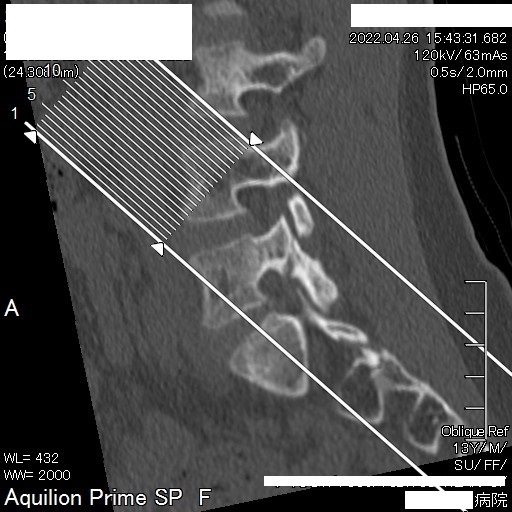

14歳 中学2年生 男子 腰椎分離症の症例

水戸市在住の中学2年生男子。サッカー競技中に腰痛を発症。整形外科にて腰椎分離症と診断される。令和4年3月 腰痛発症

4月 MRI検査にて腰椎分離症の診断。コルセット装着の保存療法にて安静加療の指示。

6月 再検査。腰椎分離症の進行が見られた。

9月 再検査。変化なし。ボルトで脊椎を固定する手術(脊椎固定術)を打診される。

10月15日 再検査にて分離部位の癒合が認められるとの所見。

11月15日 再検査にて更に分離部位の癒合が認められるとの所見。現時点で腰痛や下肢疼痛など症状の再発は無し。

今回ご紹介する症例は、半年もの間一向に改善しなかった腰椎分離症がわずか1ケ月半の間に、しかも4回の施術で劇的な改善が見受けられたことについて、病院での一連の検査が終了した後に受療者の保護者より病院での検査記録の提供を受け、発症から治癒に至るまでの詳細について時系列でお伝えするものす。また、この症例はこれらの画像提供を受ける2ヶ月前の段階で既に筋肉反射テストにより損傷部位を正確に特定し、骨の癒合を促す施術を行った結果です。この目まぐるしい回復に専門医も只々驚愕しきりだったとか。本人は手術を受けるつもりでいたようですが、我が子の体にメスを入れることを良しとしなかった母親の慈愛が正しい選択に向かったのでしょう。CTやMRIは最先端の医療検査と思われがちですが、残念ながら損傷が分ったとしてもそこには回復させる術はありません。正しい検査のみが治癒の道筋を着けることを可能とします。体は常に自力で治ろうとして様々な症状を発現しています。体の訴えに耳を傾ける時、きっと自身の治癒力が成せる奇跡のような回復劇が待っていることでしょう。当院の施術には何のリスクもありません。手術を受ける前に是非ご相談ください。